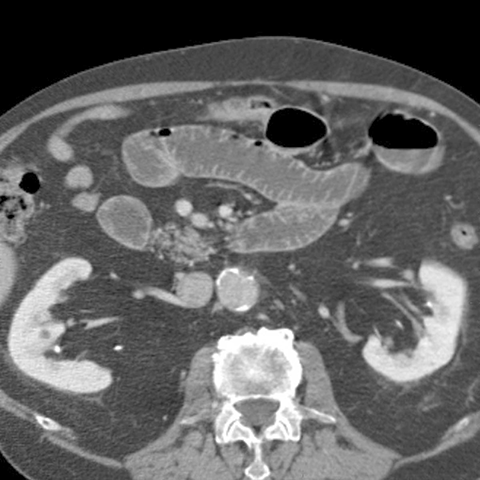

66 year-old male presents with a protruding abdominal mass and pain. [2 of 2]